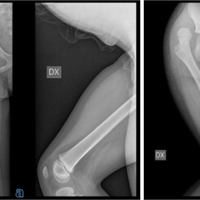

[Fig. 3: a) Pre-operative image of the injured hand b) Pre-Op X-rays of injured hand c)Post-operative image of the injured hand d) Image After Skin Grafting d) Image At 6 weeks follow-up f) Image at 6 months follow-up]

Case 3: 34 years old man, who presented within 3 hours of injury to the right hand, sustained while grinding the sugarcane pulp.